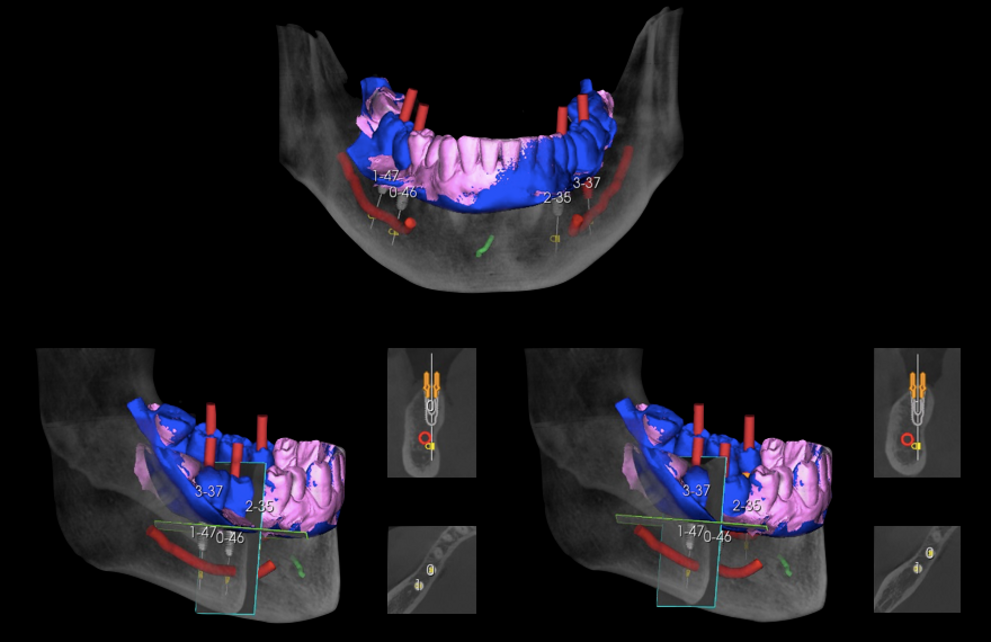

3. mascherina chirurgica: dalla fase di progettazione diagnostica alla fase chirurgica

Progettazione con software dedicato

Realizzazione e posizionamento dima chirurgica